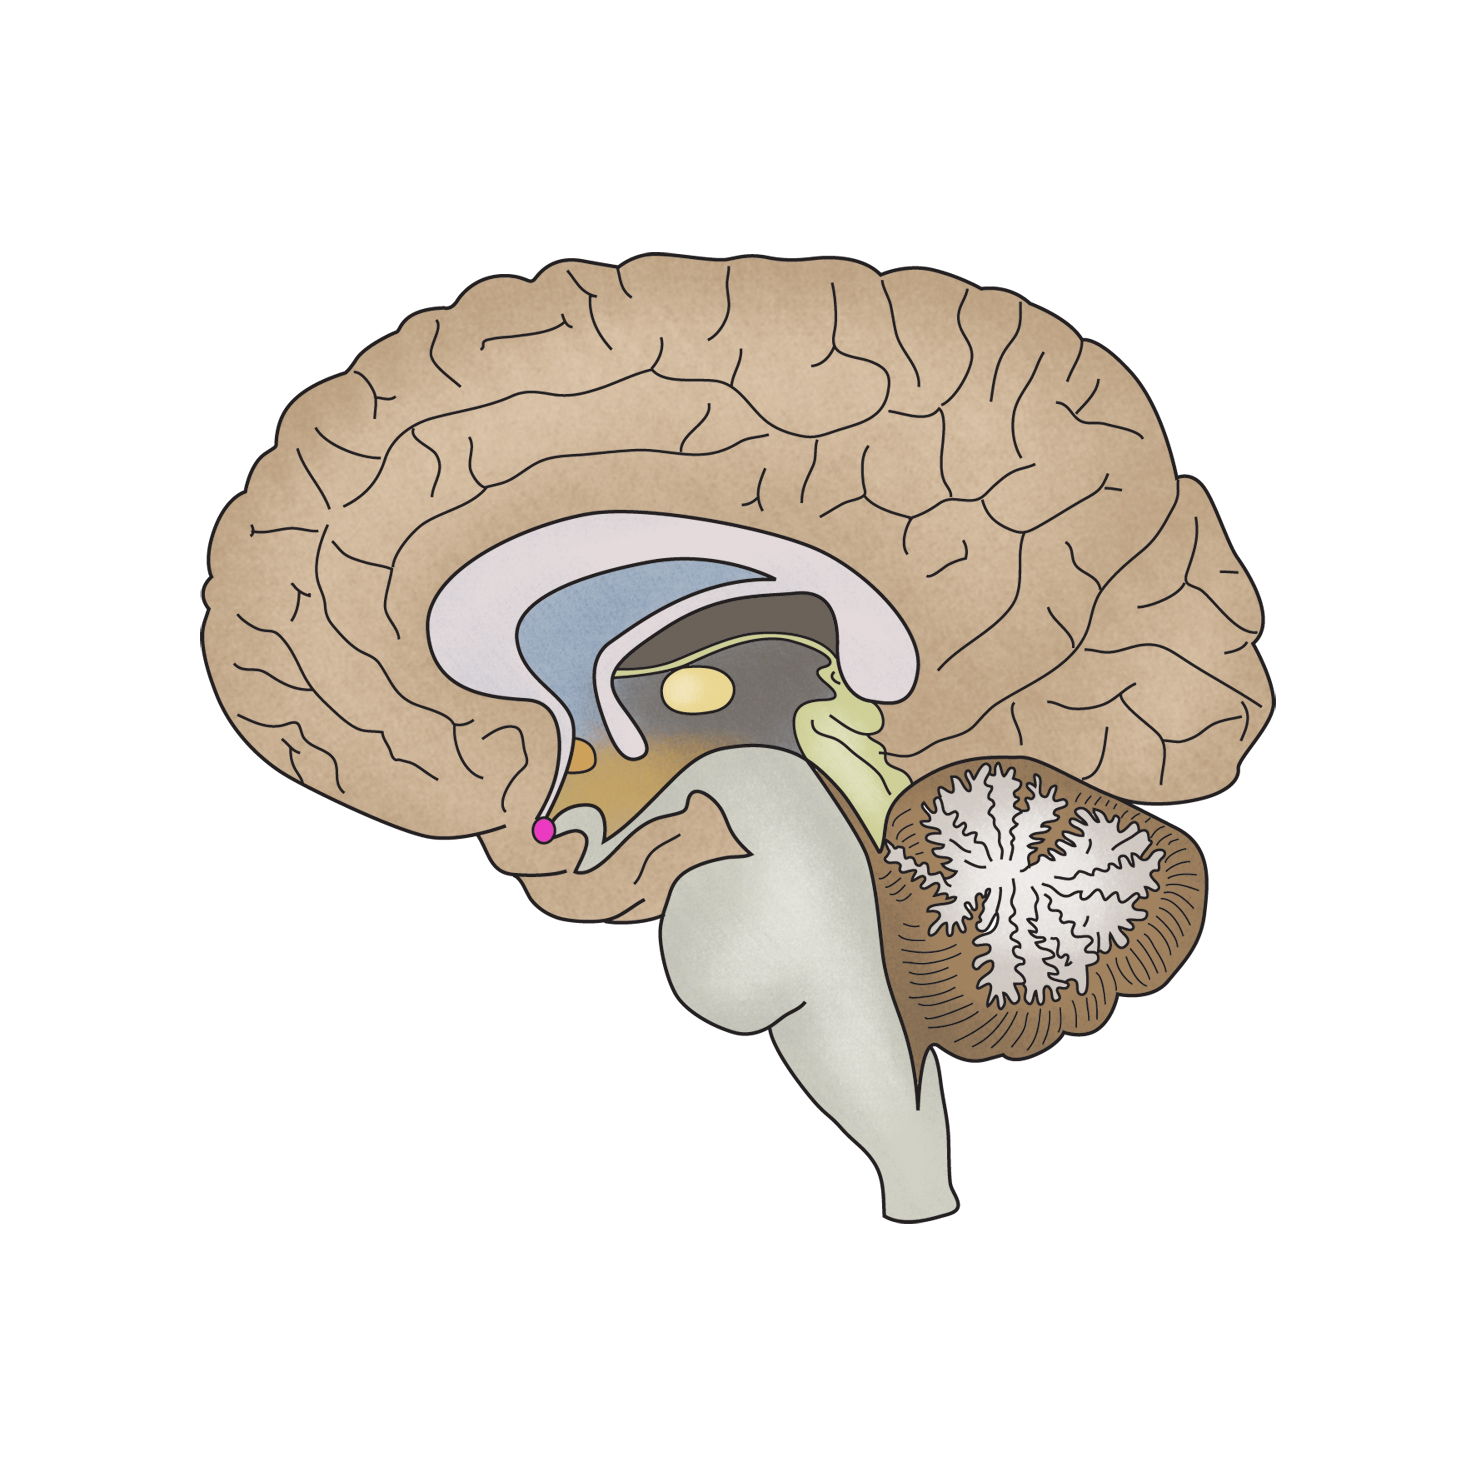

근육긴장이상증(Dystonia)

- 증상

-

근육긴장,

사경,

삼키기 곤란 ,

근육경련,

눈꺼풀의 떨림,

근육의 뒤틀림,

근육강직,

언어장애

- 관련질환

뇌졸중,

윌슨병,

헌팅톤 병,

선천성 사경

- 진료과

신경과